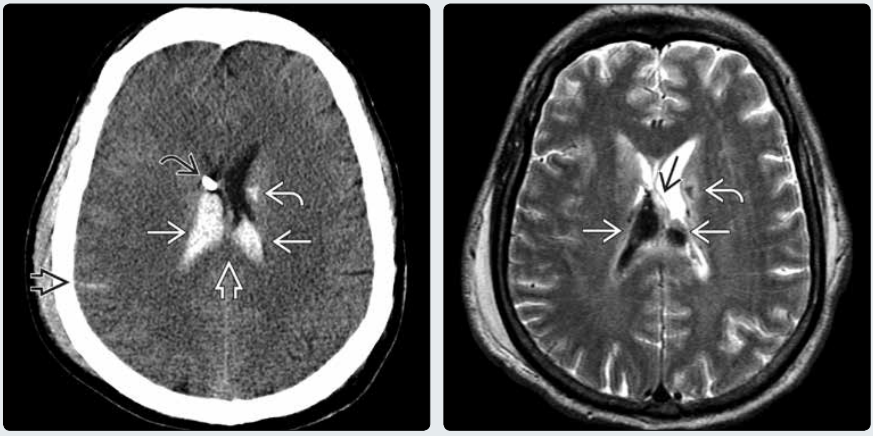

(左图)横断位 CT 平扫示双侧脑室内高密度的脉络丛实质内的脉络丛出血→。注意蛛网膜下腔出血➪,胼胝体 DAI➪,左侧尾状核出血性 DAI↪,以及脑室造瘘引流管尖端↪。

(右图)同一患者横断位 T2WI示低信号出血使脉络丛实质增大→。注意增大的右侧脉络丛出血使透明隔弯向左侧→。亦可见左侧尾状核出血性 DAI↪